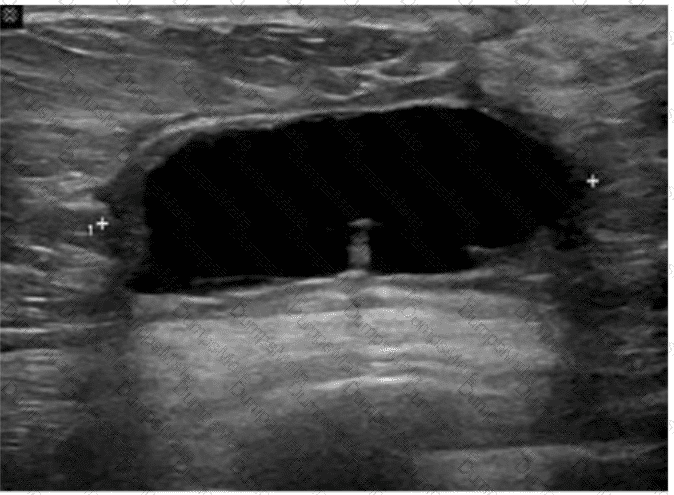

Which term best describes the common bile duct measured in this image of a postcholecystectomy patient?

AB-Abdomen Question 10

Options:

A.

Normal

B.

Dilated

C.

Inflamed

D.

Atretic

Buy Now